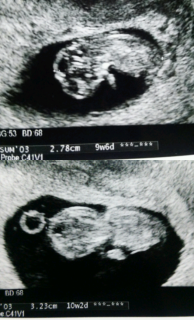

次は1か月後。2.78センチと3.23センチ。順調に育っているようです。